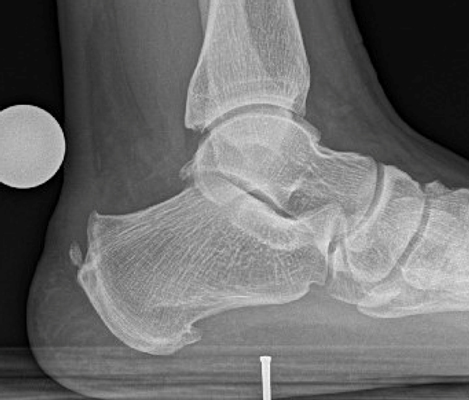

TOTAL ANKLE REPLACEMENT :: ORIF CALCANEUS :: ORIF ANKLE FRACTURE DISLOCATION :: COMPLEX BUNION AND LESSER TOE CORRECTION :: TALUS FRACTURE -1 :: TALUS FRACTURE -2 :: LISFRANC REPAIR :: COMPLEX TRIPLE ARTHRODESIS 1 :: COMPLEX TRIPLE ARTHRODESIS 2 :: MINIMALLY INVASIVE BUNION REPAIR 1 :: MINIMALLY INVASIVE BUNION REPAIR 2 :: ARTHROSCOPIC CARTILAGE REPAIR :: TENEX SPUR DEBRIDEMENT :: Haglunds Debridement and Achilles Repair